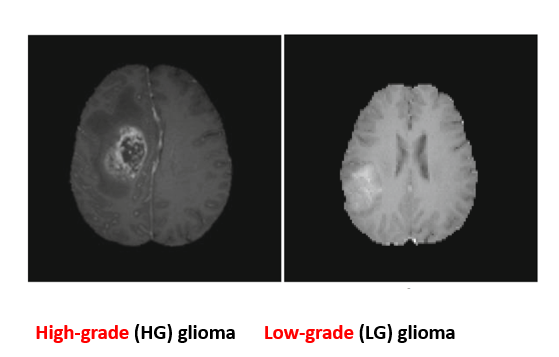

- Glioma Tumor Classification

Three-dimensional convolutional neural networks exploit volumetric MRI data to distinguish high-grade from low-grade gliomas, extracting both local and global spatial features for precise tumor grading.